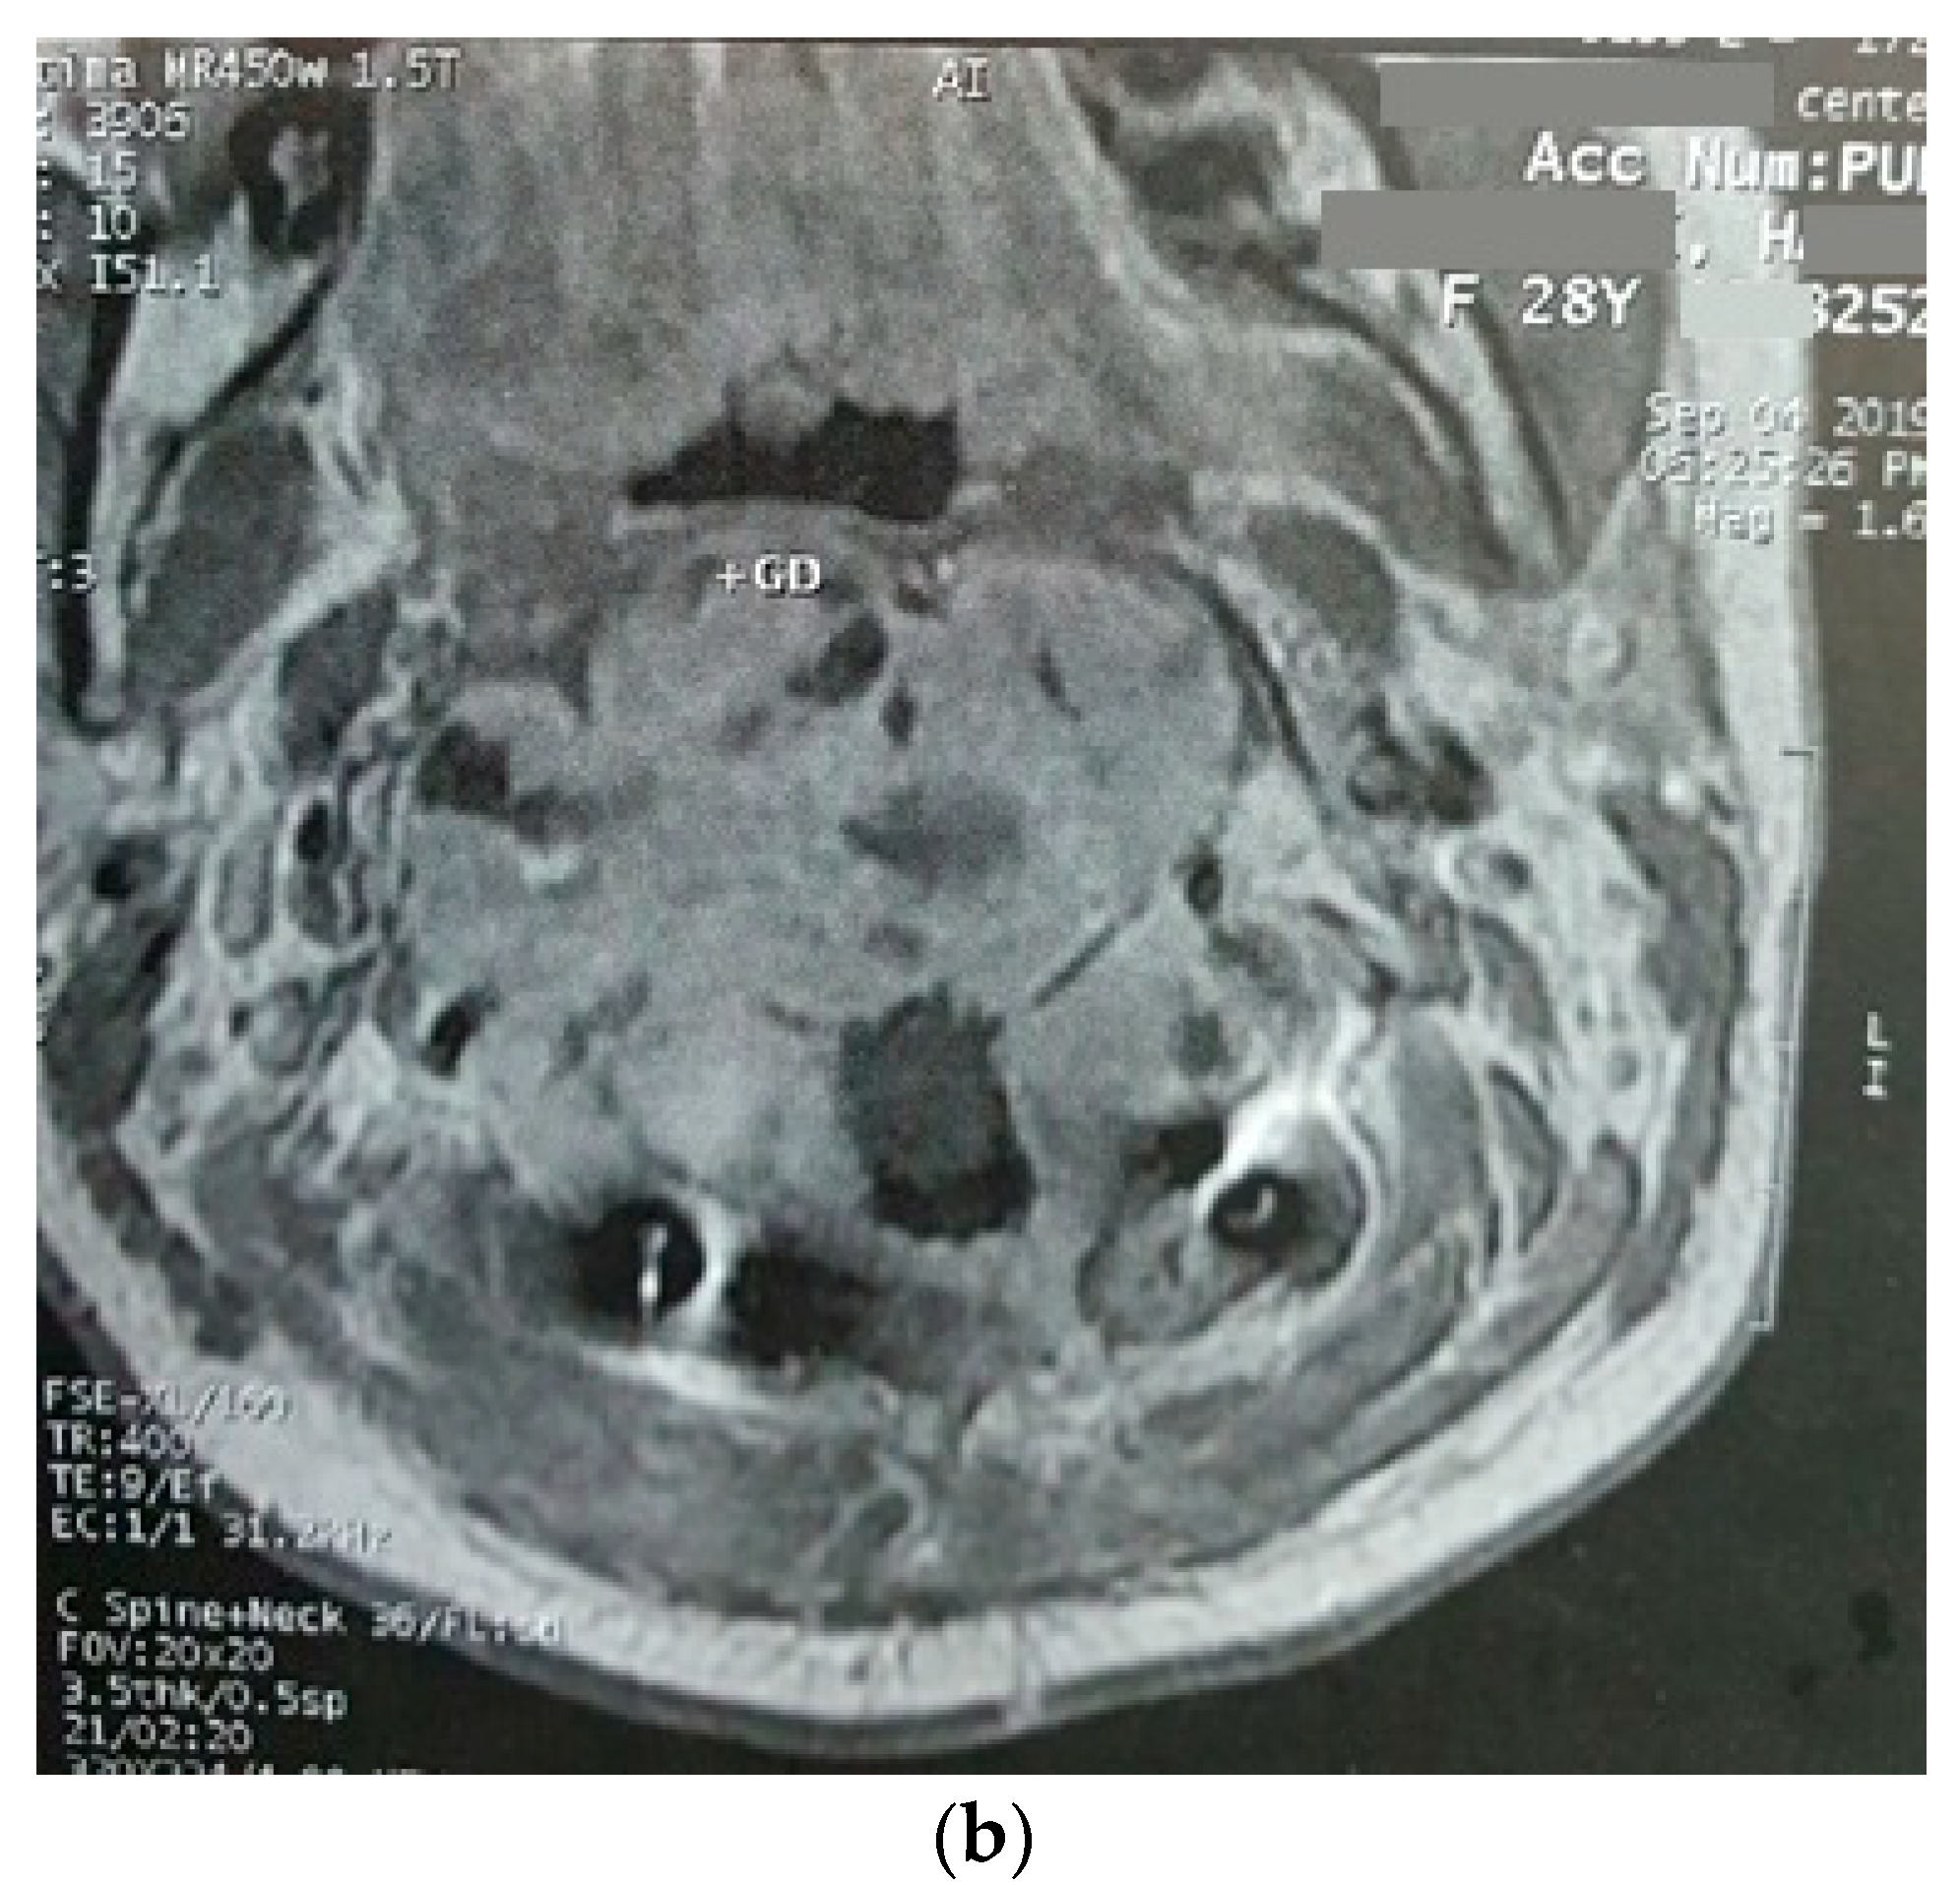

Three months later, the patient’s symptoms worsened, and she developed dysphagia. A repeat MRI showed a significant increase in the size of the tumor and a paravertebral extension (35 × 43 × 48 versus 52 × 42 × 60) (Figure 2). This time, an anterior approach was chosen for tumor decompression. There was cellular infiltration of the stroma characterized by sheets of large cells with abundant cytoplasm and rather distinct cell borders. Highly pleomorphic and sometimes hyperchromatic single nuclei were seen. Within the cytoplasm of most of the tumor cells, there were abundant partly degenerated RBCs. Scattered lymphoid cells were also present in the stroma. Some of the particles were bordered by tiny bony trabeculae. No necrosis was seen. Eight to ten mitoses per high power field with few atypical mitoses were detected, and the diagnosis of malignant HS was made. In the immunohistochemistry, cells were positive for CD45, CD43, CD68, and S100 (S100 negativity in the first operation may be due to the small size of the sample) and negative for CD3, CD20, and cytokeratin (Figure 3). The metastasis workups (thoracic and abdominopelvic CT scan) and bone marrow biopsy were normal. To deal with this new reported pathology, 25 sessions of radiotherapy (IMRT) in 5 weeks were considered for the patient to a total dose of 45Gy.

Figure 2.

Sagittal (a) and axial (b) gadolinium-enhanced MRI after the progression of the tumor that caused severe dysphagia.